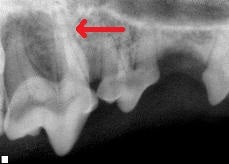

Here is a radiograph of her upper 4th premolar, with arrows highlighting the large tooth root abscess we found:

The Culprit